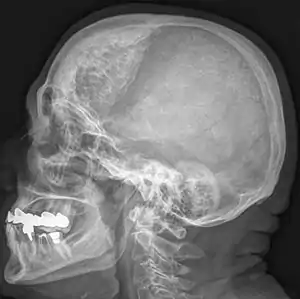

Hyperostosis frontalis interna is a common, benign thickening of the inner side of the frontal bone of the skull. It is found predominantly in women after menopause and is usually asymptomatic. Mostly frequently it is found as an incidental finding discovered during an X-ray or CT scan of the skull.

| Hyperostosis frontalis interna in a 74-year-old woman | |